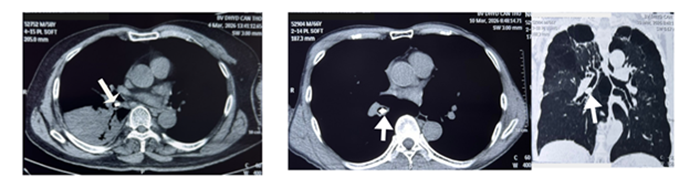

Gắp thành công 2 trường hợp dị vật phế quản bằng nội soi phế quản ống mềm tại Bệnh viện Trường Đại học Y Dược Cần Thơ